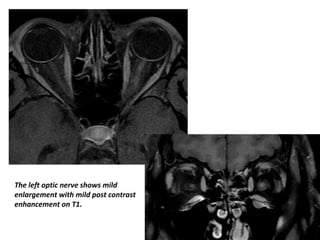

The left optic nerve shows mild enlargement

with slightly hyperintensity on T2

The left optic nerve shows mild

enlargement with mild post contrast

enhancement on T1.

The left opticnerve shows mild enlargement with slightly hyperintensity on T2

The left opticnerve shows mild enlargement with mild post contrast enhancement on T1.